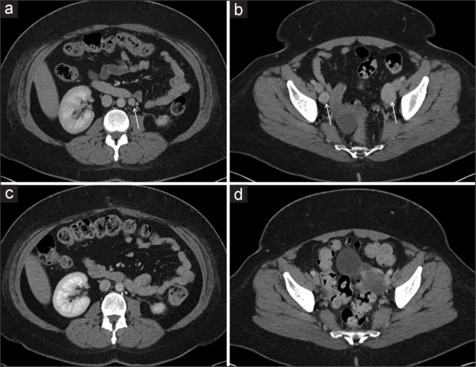

Benign metastasizing leiomyoma (BML) is thought to arise from either coelomic metaplasia of mesenchymal tissue or peritoneal seeding of uterine fibroid tissue, though its exact etiology is unknown. Herein, we present a 44-year-old Hispanic female with BML identified in the retroperitoneum in the setting of clear cell renal carcinoma. Routine follow-up computed tomography scan, 18 months after a robotic left partial nephrectomy for stage 1 renal tumor, revealed retroperitoneal (para-aortic) adenopathy. Percutaneous biopsy followed by robotic lymph node dissection confirmed the presence of BML. The patient remained asymptomatic with unremarkable imaging and laboratories within a 3-year follow-up.